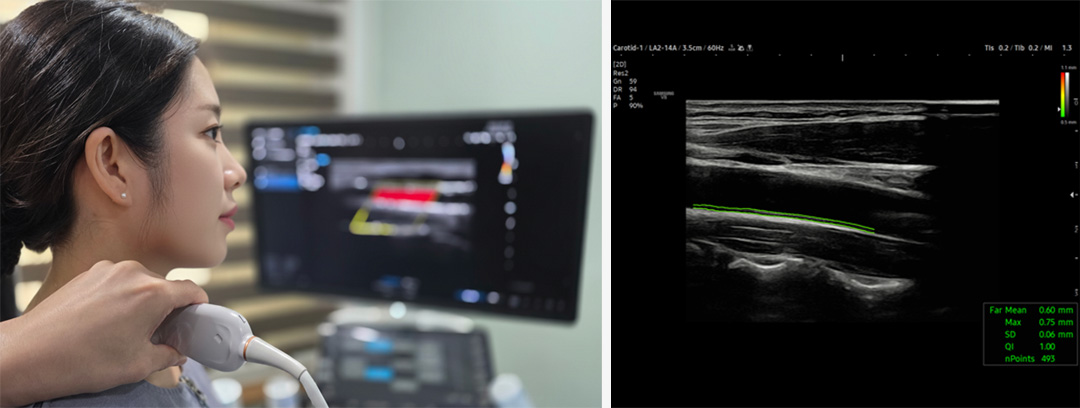

경동맥 초음파검사

뇌로 혈액을 공급하는 주요 혈관인 경동맥의 두께, 혈류 속도, 협착 여부를 초음파로 확인하여 뇌혈류 문제나 동맥경화가 이명·난청에 영향을 주는지 진단합니다.